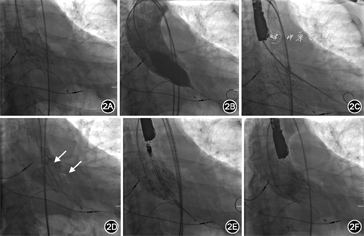

经心脏团队讨论后建议患者首选外科主动脉瓣置换术,术中探查主动脉根部,必要时考虑行带主动脉瓣人工血管升主动脉替换术(Bentall手术);次选方案可考虑再次行TAVR联合PVL介入封堵术。患者拒绝外科手术,要求介入治疗。2019年12月26日在全麻下行再次TAVR联合PVL介入封堵术。手术过程(图2):穿刺右侧股动脉置入7 Fr血管鞘,经鞘管送6 Fr猪尾导管至升主动脉窦底,主动脉造影提示重度人工瓣反流和PVL;将26 mm×4 cm NUMED球囊送至人工瓣膜假体内,快速起搏(180次/min),扩张球囊并行升主动脉造影,结果显示人工瓣无反流,瓣周反流显著,术前TTE显示人工瓣口重度反流信号,重度PVL;直头导丝(UniGlideTM,Cook Medical)经由JR 4造影导管穿过PVL隧道至左心室,交换0.036 mm×260 cm普通导丝至左心室,拟经普通导丝送5 Fr PDA/VSD输送鞘(北京华医圣杰科技有限公司)至左心室未能成功,交换超硬导丝(Amplatz Super StiffTM,Boston Scientific)至左心室,经超硬钢丝成功将输送鞘送至左心室;10~12 mm Plug Ⅰ型封堵器(北京华医圣杰科技有限公司)与推送钢缆连接,在PVL隧道左心室侧部分释放封堵器后回撤输送鞘至PVL隧道内,有阻力后封堵器近端于隧道主动脉侧完全释放;选择Vitaflow Ⅱ TAV27瓣膜支架(上海微创医疗器械公司),沿左心室钢丝送至瓣膜假体内,快速起搏(140 次/min)后“0”位释放。术后造影及TEE评估结果显示,无人工瓣反流,轻度瓣周反流。出院前复查TTE:人工瓣功能正常,轻度PVL(反流束宽度0.2 cm),中度二尖瓣反流,轻度三尖瓣反流,舒张期左心室内径6.0 cm,左心室射血分数45%。术前与术后TTE对比见图3。

本例患者首次置入自膨式瓣膜的深度合适,术后瓣膜支架展开充分,PVL的主要原因考虑与瓣叶重度团块状钙化有关,术前CTA以及TTE评估显示PVL隧道形态呈圆柱形,具备介入封堵解剖适应证,且非复杂PVL;人工瓣口反流原因不明确,首次TAVR术后即刻存在瓣口轻中度反流,此后逐步加重至重度,考虑瓣膜预装损伤可能性大,后期加重的原因不除外瓣叶血栓形成,但缺乏影像学证据。介入封堵术中使用26 mm球囊对首次植入的瓣膜行后扩张,在球囊扩张同时行升主动脉造影时,中心性反流消失但PVL无减轻,以及球囊撤出后升主动脉造影及TEE检查显示PVL仍无改善,提示球囊后扩张以及单纯“瓣中瓣”技术不能减轻瓣周反流程度。鉴于以上分析,介入策略调整为“瓣中瓣”技术解决瓣膜中心性反流,介入封堵处理PVL。考虑先行再次TAVR会给封堵治疗造成困难,建议TAVR手术前先尝试介入封堵PVL。文献回顾发现AVP2适合圆柱形PVL封堵,国产Plug封堵器的形态特征与之相似,故选择该类型封堵器。从以往介入封堵外科瓣膜置换术后PVL的经验中总结出,在释放器械之前,建议进行以下安全性检查:识别任何残余漏(轻度及以下反流);通过牵拉和/或推动输送线缆来测试封堵器械的稳定性;主动脉瓣PVL介入封堵时需要确认冠状动脉的通畅性。